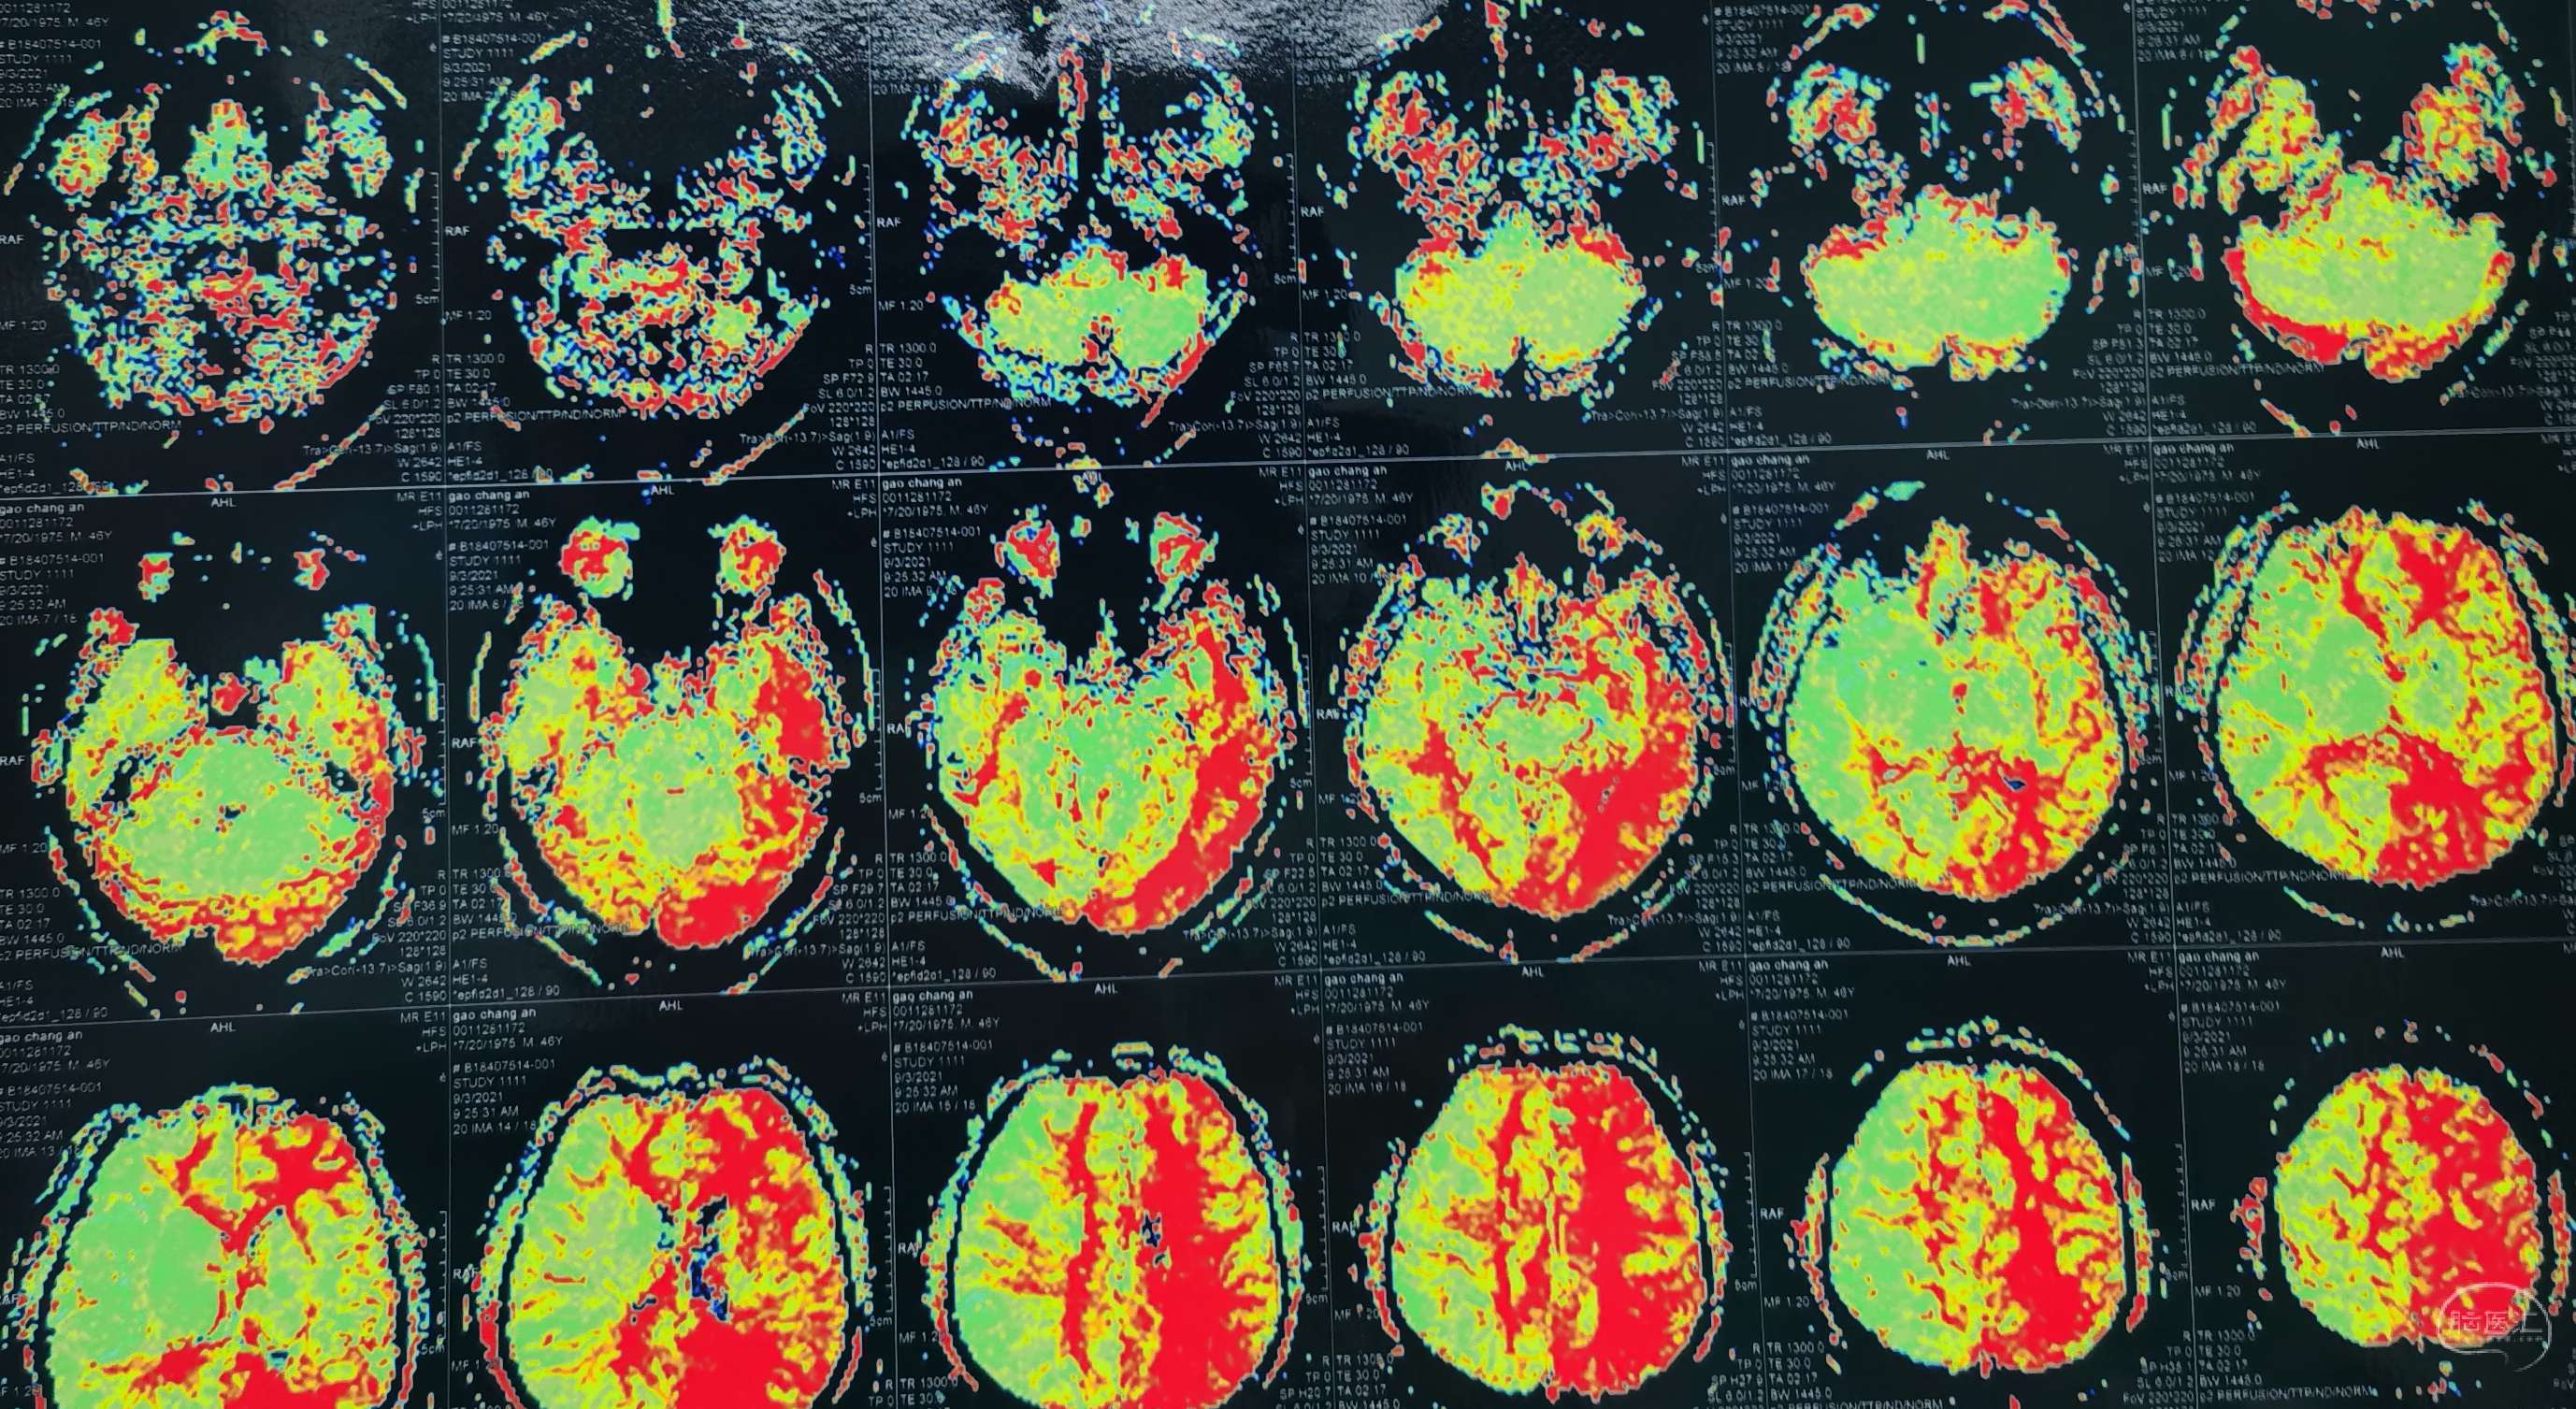

磁共振灌注提示:双侧大脑半球低灌注改变。

DSA示:左侧大脑前、大脑中动脉闭塞,烟雾样血管形成。

DSA示颞浅A未向颅内代偿。

术前彩色荧光造影示:缺血区。

颞浅A-M4端侧吻合14针,荧光造影显示:吻合血管通畅。

术后荧光造影示:缺血改善。